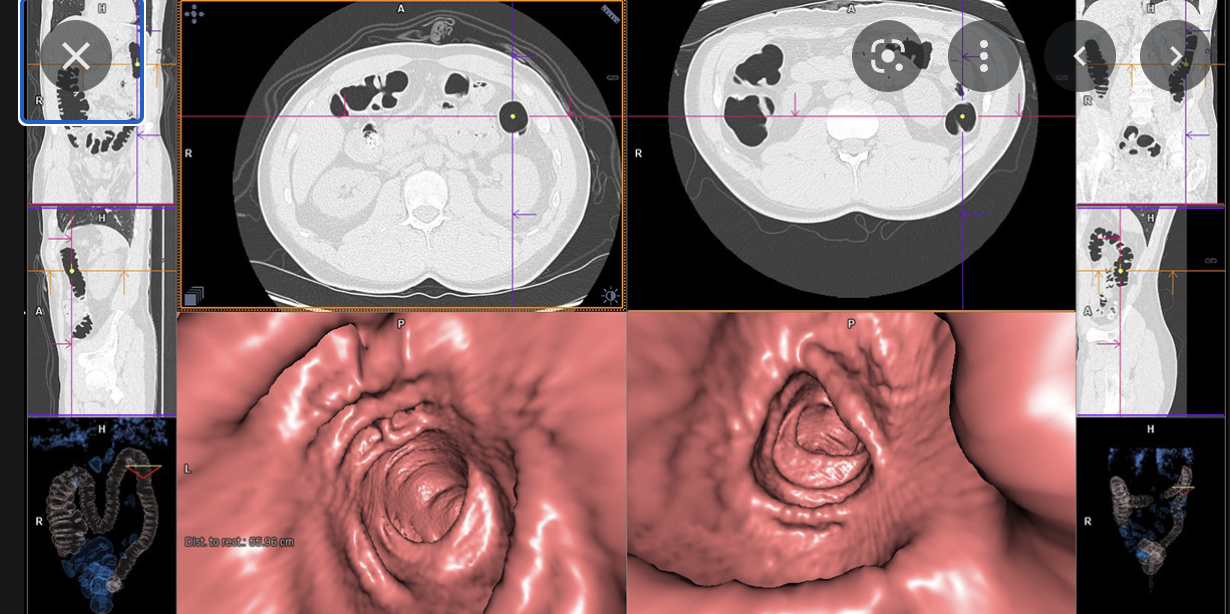

3 - CT scan

• CT colongraphy is best

In a patient with stage 1 or 2 diverticulitis, which is associated , called the Hinchey classification, what is the best way to diagnose the patient? 1 - colonoscopy 2 - X-ray 3 - sigmoidoscopy 4 - CT with contrast

4 - CT with contrast - generally barium enema

There are 4 stages of diverticulitis, called the Hinchey classification used to describe perforations of the colon due to diverticulitis. The diverticulum can perforate from a pin hole size to >1cm. This can lead to gaseous and faecal contents causing peritonitis.Which 2 imaging modalities can detect this? 1 - ultrasound 2 - CT scan 3 - X-ray 4 - MRI

2 - CT scan 3 - X-ray - scan must be erect - we can see pneumoperitoneum